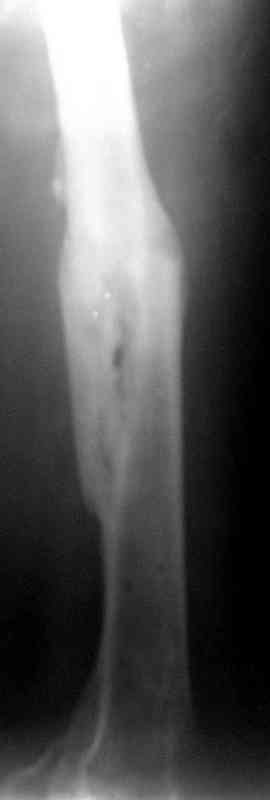

месяцев дистракции укорочение левого бедра удалось полностью устранить. 22.02.00, т.е. через 2 месяца после повторного остеосинтеза, больному произведено дистальное блокирование штифта двумя винтами и демонтирован аппарат Илизарова. В течение 2 недель после операции больной ходил с помощью костылей, потом 2 недели с тростью. Опороспособность и функция оперированной конечности полностью восстановились через 4 недели после операции.

Фиксаторы удалены через 12 месяцев после операции, выполненной по поводу замедленной консолидации перелома бедра с его укорочением.

На финальных снимках видно - сращение прям таки железное. Если Вы не устали отвечать, осмелюсь задать еще вопрос - что-то принимал пациент в целях ускорения сроста (кальций, режим питания). Интересны также вопросы восстановления функций конечности - в какой период были рекомендованы группы упражнений для восстановления основных групп мышц?